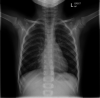

Chest X-ray taken less than 24 hours later, showing bilateral perihilar infiltrates extending into the lower zones.